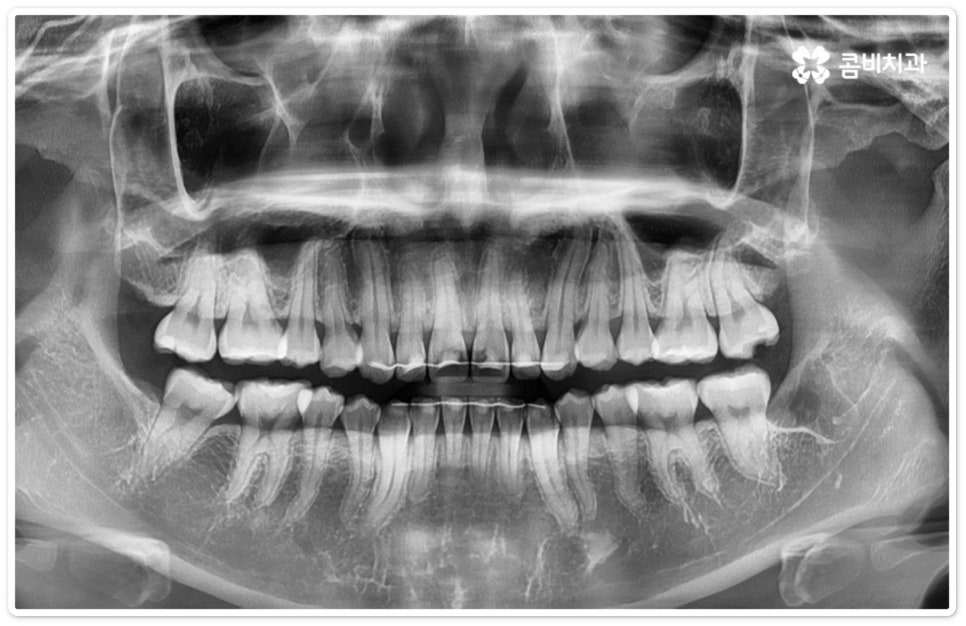

사랑니의 개수, 위치, 각도나 뿌리의 형태, 매복 깊이 등은 사람마다 다른데 그 중에서 특히 완전히 매복된 상태로 비스듬히 누운 채 자리잡은 아래 사랑니의 경우 턱을 가로지르는 하치조 신경과 가깝기 때문에 누운사랑니발치 시 신중을 기하지 않으면 혹시 모를 부작용인 감각 이상을 초래할 수 있으므로 뛰어난 해부학적 지식과 풍부한 임상 경험, 세심한 기술력을 가지고 있는 숙련된 의료진에게 치료를 받으시길 권유드리고 있어요. 혹시라도 신경 손상이 발생하게 되면 입술이나 턱이 마취된 듯 침이 흘러도 감각이 없거나 양치질을 할 때 물이 입술밖으로 세어나가는 상태가 유발될 수 있으니 조심해야 할 거예요.

매복 형태의 사랑니는 잇몸을 절개하고 발치해야 하며, 특히 깊숙하게 누운사랑니발치 시에는 신경을 건드리지 않도록 사랑니를 조각내어 조심해서 빼내야 할 뿐 아니라 환자분들의 상태에 따라 잇몸뼈를 조금씩 삭제해야 할 수도 있기 때문에 이러한 고난도 시술에는 주변 조직의 손상을 최소화하고 혹시 모를 부작용의 위험을 줄이며 출혈 및 통증이 커지지 않도록 하기 위해서 시술자의 높은 숙련도가 더욱 요구된다고 할 수 있어요. 또한 매복된 사랑니의 각도, 뿌리 형태, 인접 치아와의 관계, 신경 위치 등을 정확하게 파악하고 체계적인 맞춤 계획을 세워 무리하지 않게 사랑니 발치 수술을 진행하기 위해서 정밀 진단이 가능한 3D CT 장비가 있는 치과에서 꼼꼼한 검사부터 받아보는 것이 중요할 거예요.